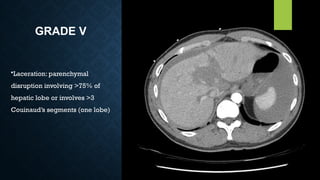

GRADE V

•Laceration: parenchymal

disruption involving >75% of

hepatic lobe or involves >3

Couinaud’s segments (one lobe)

GRADE V •Laceration: parenchymal disruptioninvolving >75% of hepatic lobe or involves >3 Couinaud’s segments (one lobe)